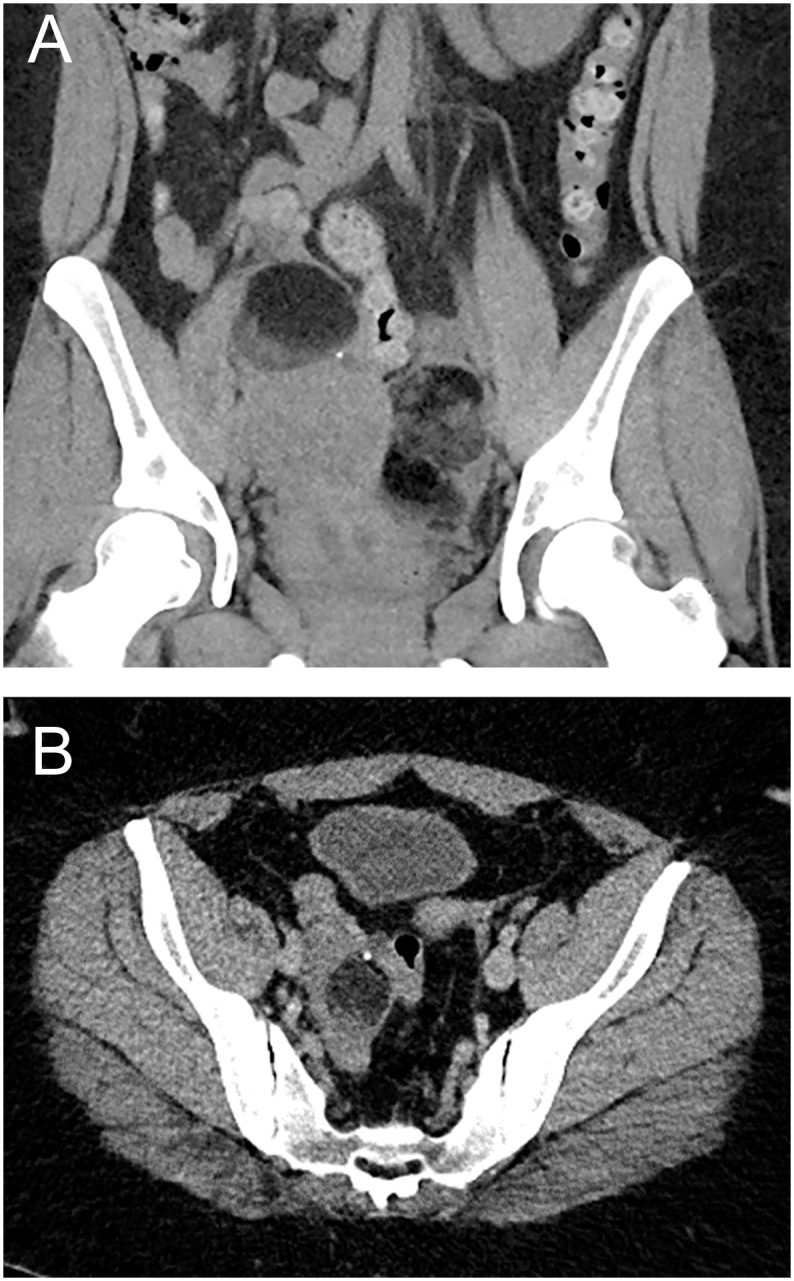

Summary: HDR syndrome is a rare, heterogeneous genetic disorder characterised by a triad of hypoparathyroidism, sensorineural deafness, and renal disease. The defect in most patients is caused by deletions in chromosome 10p14 or mutations in the GATA3 gene. HDR syndrome is also associated with several atypical features, including eye, skin, neurological, cardiac, gastrointestinal, and urogenital involvement. We report the case of a 27-year-old Caucasian woman with HDR syndrome (GATA3 NM_001002295.1: c.977C>A p. (Thr326Asn)), who presents with multiple atypical associated features. She has also had recurrent benign ovarian cystic teratomas, although it is unclear whether these are related to HDR syndrome, as this has never been reported.

Learning points: HDR syndrome is a rare autosomal genetic disorder characterised by a triad of hypoparathyroidism, sensorineural deafness, and renal disease. It may be associated with atypical features involving various organs, which will require investigation and management. There is a paucity of evidence and guidance on managing hypocalcaemia in HDR syndrome. Given that HDR syndrome causes agenesis rather than a receptor issue, calcium levels should be targeted between 2.0 and 2.2 mmol/L, similar to the management of hypoparathyroidism caused by surgery or autoimmune disease.